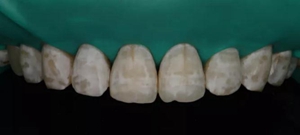

1,術(shù)前照片,全口氟斑牙,前牙表面釉質(zhì)白堊色+黃色斑點(diǎn)+凹坑缺損。

術(shù)前正面?zhèn)让嬲掌?/span>